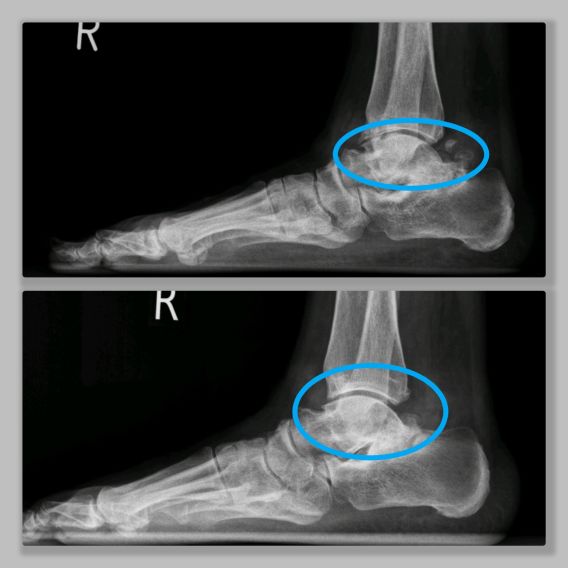

Slijtage van de enkel: Enkelarthrose

Het enkelgewricht wordt gevormd door drie botten: het scheenbeen (de tibia), het kuitbeen (de fibula) en het sprongbeen (de talus). Het scheenbeen is het grootste en sterkste bot van het onderbeen. Het kuitbeen is een stuk kleiner en smaller en zit aan de buitenzijde van de enkel. Het enkelgewricht (het bovenste spronggewricht) is een hevel waardoor de voet omhoog kan buigen en naar beneden kan buigen. Door deze beweging kunnen wij goed lopen en ook bijvoorbeeld makkelijk een trap op en af lopen. Mensen met klachten van het enkelgewricht hebben dan ook vaak pijn aan of een onstabiel of onzeker gevoel bij het traplopen maar soms ook al bij het normale lopen. Rondom het enkelgewricht zitten sterke banden , de ligamenten, die het enkelgewricht stabiel maken. Het sprongbeen, de talus, rust op het hielbeen, de calcaneus. Het gewricht dat gevormd wordt tussen deze twee botten heet het onderste spronggewricht, het subtalaire gewricht. Dit gewricht zorgt ervoor dat de enkel naar buiten en binnen kan kantelen. Deze beweging is bijvoorbeeld nodig als wij op een oneffen terrein lopen.

Het is belangrijk onderscheid te maken tussen het bovenste spronggewricht en het onderste spronggewricht. Slijtage kan op beide niveaus plaatsvinden.

Bij het bovenste spronggewricht ontstaan er botuitsteeksels, met name aan de voorzijde van de enkel: hierdoor kan er een beklemming ontstaan bij het omhoog bewegen van de enkel. De enkel stagneert, ook kan er een klein stukje van deze uitsteeksels afbreken, dit stukje kan dan gaan zweven in de enkel en kan ook een blokkade van de enkel geven. De slijtage van de enkel kan zowel aan de voor- als de achterzijde van de enkel zitten. Vaak staat de enkel een beetje uit het lood, hierdoor wordt bijvoorbeeld de binnenzijde van de enkel meer belast in vergelijking met de buitenzijde. De slijtage in de enkel is dan vaak ook niet overal even erg.